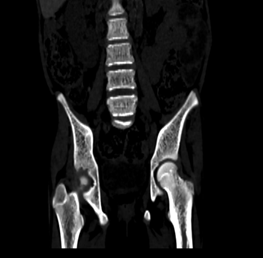

The visualized axial

skeleton demonstrated coarsened trabeculae characteristic of thalassemic bone

changes, with no paravertebral masses identified (Figure 2).

Fig 2(a) Fig 2(b)

Figure

3(a,b): Bone window

CT images of the abdomen in the sagittal and coronal plane window showing

coarse trabeculations in the axial skeleton

Skeletal manifestations

The

coarsened trabecular pattern observed on CT represents the skeletal response to

chronic anemia and extramedullary hematopoiesis. Marrow expansion led to

cortical thinning and altered trabecular architecture, predisposing patients to

pathological fractures10,16.